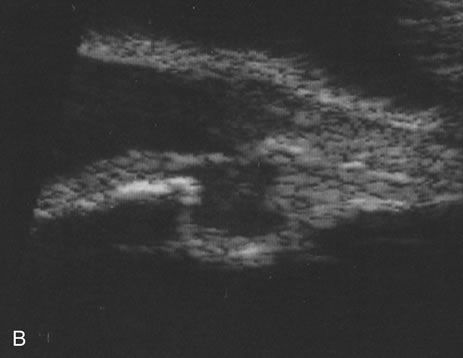

Unfortunately, imaging studies are not always diagnostic. The A- and B-scans shown in Figures 3 and 4 were from a patient with unilateral media opacity referred for evaluation and treatment of a presumed uveal melanoma. Occasionally, if the cataractous lens is scanned tangentially, artifact can occur. A repeat ultrasound at our institution was negative for tumor, and the referral ophthalmologist who performed a cataract extraction noted that no tumor was present and that the patient has an excellent visual outcome. In contrast, the patient shown in Figure 5 was referred with a presumed uveal melanoma with secondary inflammation and a history similar to that described for the patient shown in Figure 111 Ultrasound and CT examinations were not diagnostic. Because the eye was blind and painful, it was enucleated, and an extremely necrotic uveal melanoma was noted histologically. In some necrotic melanomas, the fundus cannot be visualized and the diagnosis cannot be established with imaging studies. Very rarely, a necrotic uveal melanoma can produce sufficient pigment dispersion into the vitreous to obscure the correct diagnosis.12